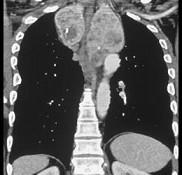

问题 男,33岁,颈部包块半年余,可随吞咽上下移动,请结合影像学检查,选出最可能的诊断 ( )

选项 A.胸腺瘤 B.淋巴瘤 C.纵隔畸胎瘤 D.淋巴管瘤 E.胸骨后甲状腺肿

答案 E